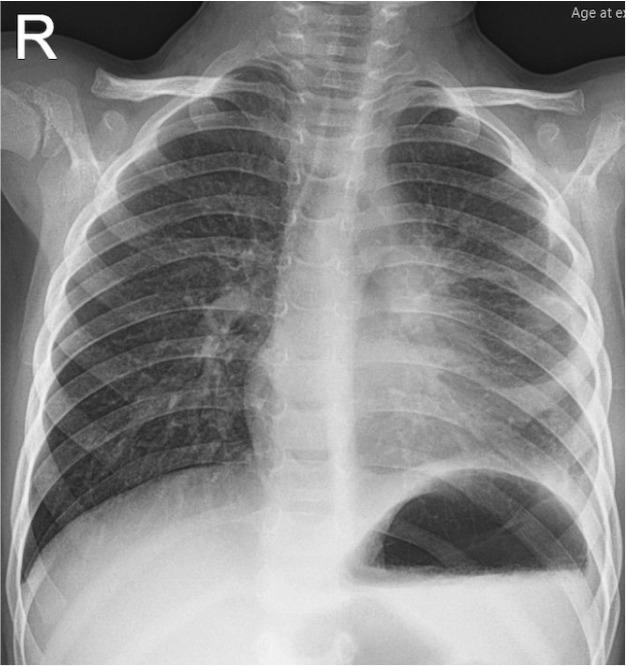

Teaching point: This is a review of the typical radiological features of a mature mediastinal teratoma with a rare presentation of spontaneous pleural rupture.

Abstract Image